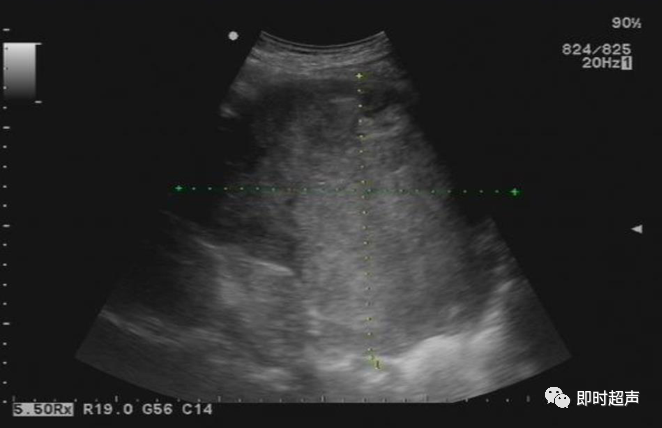

• GIST的发病机制与KIT信号通路的激活有关。• KIT是一种酪胺酸激酶跨膜受体蛋白,未经“装配”过的KIT蛋白是一种非活化的单体,参与细胞膜形成。几乎所有GIST都表达了KIT蛋白,而且大多突变的KIT基因保留了表达KIT蛋白的特性。c-kit内的突变主要见于恶性病例,特别是外显子11的点突变,还有外显子9、13和17,可以导致本质的或配体独立的c-kit激活,引发细胞的无序增殖和凋亡。这些具有功能的突变是GIST发病机理的关键,并且与肿瘤的恶性程度和预后较差相关。• GIST约75%发生于50岁以上老年人,中位年龄为58岁,无明显差异。• 可以发生在消化道从食道到肛门的任何部位,偶尔可原发于网膜、肠系膜和腹膜后,约50%发生在胃,25%发生在小肠,不足10%发生于食管、结肠及直肠。大体观察:肿块多境界清楚,类圆形,结节状,部分有假包膜。切面灰白、灰红,质韧,部分质嫩呈鱼肉状,伴有出血、坏死、囊性变。• 肿瘤组织主要由两种细胞组成,一种为长梭形细胞,细胞质丰富,嗜酸性,细胞核呈梭形或杆状;另一种为上皮样圆形或多角形细胞,细胞肥胖,胞质少。两种瘤细胞常呈束状、编织状或旋涡状排列。• 部分病例细胞异型明显,核分裂象增多,可见病理性核分裂象和瘤巨细胞。梭形细胞界不清楚,胞质丰富,淡染,轻度嗜伊红或略嗜碱,可有纤细、长梭形、短梭形或胖梭形、卵圆形,可见核仁。细胞核两端钝圆,部分病例胞质呈空泡状,位于核一端形成核端空泡胞,多呈交叉束状、旋涡状、席纹状及栅栏状排列。上皮样细胞胞浆丰富或透亮,多呈弥漫片状、束状或巢状排列。肿瘤间质可有出血、囊性变、坏死及黏液变,可见炎性细胞浸润。CD34抗原是一种115kd的糖基化蛋白,50%~80% GIST的CD34表达为阳性,CD34对鉴别GIST和典型的平滑肌瘤,神经鞘瘤还是非常有用的标记物,因后两者的CD34一般是阴性的。但CD34在诊断GIST上其特异性受到限制,一般情况下CD34多与CD117联合应用,方能提高GIST的诊断率。• 与肿瘤大小、发生部位、肿物与肠壁的关系以及肿瘤的良恶性有关。• 肿瘤较小者(直径小于2cm)常无症状,往往在体检和其它手术时无意中发现。• 肿瘤发生于胃肠道腔内时大多表现为呕吐、腹痛及消化道出血,而发生于胃肠道腔外的则主要表现为腹部包块。• 最常见的临床症状是中上腹部不适、腹部肿块及便血。• 对于临床发现的消化道(包括肠系膜、网膜、后腹膜)实体肿瘤,在排除其他常见肿瘤后,才考虑GIST。目前,诊断GIST有三条标准:③肿瘤组织具有梭形细胞和上皮样细胞两种基本细胞成分的病理学特征。这是诊断GIST金标准。CD117阳性者或CD117阴性而CD34阳性者,且伴平滑肌和神经双向分化或无分化者,可诊断为GISTs;以Desmin和SMA强阳性,而CD117阴性诊断为平滑肌肿瘤;以S-100阳性,CD117、Desmin、SMA均阴性诊断为神经鞘瘤。• GISTs的分型与组织学良恶性的关系:研究证实GISTs非单一分化的肿瘤,具有多向分化。• 当前GISTs的良性、交界性和恶性判断标准多参照Amin等提出的标准:②交界性:核分裂<5/50HPF,但肿瘤>5cm;• 另外研究显示,平滑肌型大多数为良性,少数为交界性和恶性,神经源型为恶性,双向分化亚型和未分化型为交界性和恶性,提示GISTs的分化型与其良恶性之间有一定关系。• 胃间质瘤早期多局部侵犯,后期出现肝转移和腹腔内种植,小肠间质瘤早期即可出现转移• 主要有超声扫描(检出率30%左右)、纤维内镜、超声内镜、CT、MRI、普通X• 线检查(胃肠钡餐造影、小肠插管气钡双重造影)、选择性血管造影检查等。• 不同部位的GIST,各种检查方法的敏感性不同。以CT检查为佳,尤其是螺旋CT,分辨率最高,可以三维重建,直接显示肿瘤大小、形态、密度、内部结构、边界,对邻近组织的侵犯也看得很清楚,同时还可观察其他部位的转移灶,有利于分期、鉴别与诊断。• MRI具有多轴成像及反映肿瘤内部成分的优点,尤其是动态扫描及各种新的扫描系列的出现更使其可以普及应用。• DSA检查对于GIST,特别是有消化道出血的患者更有价值。• 上述影像学检查表现并非特异性,与胃肠道平滑肌肿瘤、神经源性肿瘤鉴别困难。明确诊断要依赖病理免疫组化等手段。• 超声图像特征 肿物体积较小者(直径< 5. 0 cm )多为实性病变, 呈类圆形, 边界清晰, 内部回声多为较均匀的低回声。• 肿物体积较大者(直径> 5. 0 cm ) 多为混合性病变,呈不规则圆形或分叶状, 多数边界尚清晰, 以实性为主的病变内部为不均质中低回声伴不规则液性区及斑点状强回声; 以囊性为主的病变囊壁较厚,有分隔, 部分囊腔内可见点状、团状低回声。CDFI显示肿物实质回声内血流均较丰富。病例1:患者男, 62岁。自扪腹部包块2月余,包块增大20天就诊。查体:腹部平坦,无腹壁静脉曲张,无胃肠型及蠕动波,腹肌软,剑突下5cm处及左肋缘下可触及一质韧包块,大小约15*12cm,活动度差,边界尚清,包块深压痛,全腹无反跳痛。化验检查AFP:3.66(1.09-8.04)ng/ml,CEA:2.85(0-5)ng/ml。体格检查:一般情况良好,全腹软、平坦,腹部无压痛。超声检查:患者仰卧位时左上腹于胰尾前方可见一大小约6. 1 cm ×5. 8 cm ×5. 3 cm实性均质低回声,形态规则,包膜完整,边界清晰,活动度大;右侧卧时,肿块移至胰头右前方(图1) ;于其内探及丰富血流信号。体格检查:一般情况良好,腹丰满,上腹部有轻压痛,未扪及明显肿块。超声检查:患者仰卧位时左上腹于胰尾前方、脾门处可见一大小约10. 0 cm×8. 8 cm×7. 6 cm 实性低回声(图2) ,形态规则,包膜完整,边界清晰,肿块活动度大;右侧卧时,肿块移至左肝下间隙,回声尚均质;于其内探及较丰富血流信号(图3) 。图3 腹腔低回声肿块位于左肝下间隙,于低回声肿块内探及较丰富血流信号向壁外生长的胃肠道间质瘤, st为胃腔,箭头所指为胃壁, T为向外生的肿瘤• 胃间质瘤的定位准确率要高于十二指肠及小肠间质瘤,这主要是因为胃的解剖位置相对固定,且通过饮水使胃腔充盈,可清晰的显示胃壁的各层结构及肿块与胃壁的关系。肿块多表现为粘膜下、肌层或浆膜下低至中等回声团块,可向腔内、腔外或腔内外生长。但当肿瘤较大或浸润周围脏器时,超声定位仍有困难, 因此,超声如发现上腹部肿块且怀疑来源于胃者,应尽可能嘱其饮水充盈胃腔,并多角度、多切面观察肿块与周围脏器的关系,以提高定位的准确性。• 十二指肠间质瘤的定位亦较准确,但降部的外生性肿块常与胰头粘连而误诊为胰腺肿瘤回声均匀且位置较深的间质瘤亦可能误为胰头周围淋巴结。• 空、回肠间质瘤常因肿块较大,多发,位置不固定而难以定位,往往误诊为腹、盆腔或腹膜后肿瘤,超声检查如发现肿块局部肠壁增厚,肿块与肠道随呼吸同步运动时可作出定位诊断。• GIST的声像图表现有助于其良、恶性的鉴别:良性肿瘤多体积较小,圆形或椭圆形,回声均匀,边界清晰。恶性肿瘤多较大,呈不规则分叶状,回声不均匀,内部易出血、坏死、囊变。• 肿瘤长径与肿瘤内部是否出现无回声区在良、恶性病变之间的差异有统计学意义,是判断良恶性的有效征象。• 如以肿瘤长径>5cm为诊断恶性标准,其敏感性、特异性及准确性均较理想。超声可为临床提供胃肠道间质瘤的部位、大小、边界、回声等较多有用信息,一部分病例可作出定位、定性诊断,并可在术后或复发患者药物治疗期间对其进行动态观察;CDFI方便快捷、无需造影剂即可对间质瘤周边及内部血流进行观察,可为临床医师提供肿瘤血供情况。但未发现腹腔或肝脏转移时,超声判断胃肠道间质瘤性质有一定难度。• 目前临床上对GISTs的治疗效果并不十分满意。治疗仍以手术为主,对无法手术切除或已有转移的GISTs患者进行甲磺酸伊马替尼化疗。• 手术方式取决于肿瘤大小、部位和术中冰冻切片结果等。• 发生在胃的间质瘤,可首选胃大部切除术;发生在十二指肠的间质瘤可行保留胰头的十二指肠切除术或胰十二指肠切除术;发生在小肠的间质瘤可行肿瘤肠段切除术;发生于结肠的间质瘤可行左半或右半结肠切除术;发生于直肠的间质瘤可行肿瘤局部切除术。一般情况下无需淋巴结清扫。• 术后随访监测,复发者单个病灶可考虑手术切除;多发或转移特征者应试行甲磺酸伊马替尼化疗,并监测肿瘤大小及数目的改变。• 随着分子靶点药物进入肿瘤临床,一种小分子化合物———酪胺酸激酶受体抑制剂,美国称为Gleevec,欧洲叫做Glivec(格列卫),在治疗GIST和慢性粒细胞白血病方面有其独特的作用。已知细胞膜表面上皮生长因子受体酪胺酸激酶抑制剂大致分为两大类:一类是小分子化合物;另一类是特异性抗体。利用抑制酪胺酸激酶的活性,对处于增殖期状态的病变具有治疗的作用。Glivec在体外、体内和细胞水平都可强烈抑制酪胺酸激酶的活性,是干细胞因子(SDCF)受体KIT的强抑制剂。• Glivec推荐用量为400mg(4片),每日一次, 3个月为一疗程。如服3个月后无效可加至600mg/d~800mg/d(6~8片)[18];若仍无效果不再增量应停止治疗。• Glivec治疗进展转移的GIST总有效率为50%左右,比传统化疗有效率高十倍以上;肿瘤生长控制率达80%以上,起效最快在服药后24h之内,使症状改善如疼痛缓解;平均起效时间为13周(约3个月)。患者体力状况改善是又一突出效果。2/3患者治疗后无症状可如健康人生活工作。• Brainard等研究发现间质瘤预后差的前两位因素为肿瘤大小和核分裂象,故对于间质瘤直径>5cm和核分裂象>5/50HPF的患者应给予口服Glivec。最近,Liu报道口服Glivec治疗可使85%患者的病情得到控制。